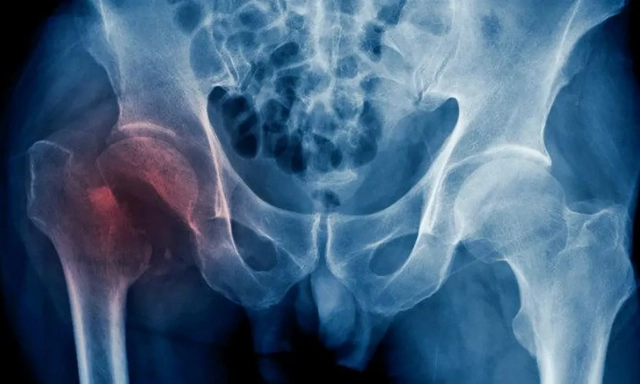

La cadera es una articulación formada por la unión del fémur (hueso del muslo) y el acetábulo (parte de la pelvis). Cuando decimos que un paciente sufre una fractura de cadera, en realidad, hacemos referencia a la extremidad proximal del fémur. Esta lesión es muy frecuente en las personas mayores, ya que tienen los huesos más frágiles por la osteoporosis y mayor riesgo de caídas por problemas de equilibrio o movilidad.

En cuanto a la técnica quirúrgica empleada para tratar la fractura de cadera, existen dos opciones principales: la fijación de la fractura (mediante distintos tipos de osteosíntesis- clavos, placas, tornillos-) y el reemplazo de la articulación por una prótesis. La elección de una u otra depende fundamentalmente, del tipo y la localización de la fractura , aunque cada caso es evaluado detalladamente por el profesional.

“De forma muy generalizada y refiriéndonos al tema en cuestión, podemos decir que la fijación de la fractura se suele realizar aquellas que afectan al macizo trocantérico (extracapsulares), mientras que optamos por una prótesis en aquellas que la zona afectada es el cuello femoral (intracapsulares). "En cualquier caso, el objetivo es lograr una estabilidad óptima que permita al paciente apoyar y caminar lo antes posible, salvo en casos individualizados”, explica el doctor Badillo.